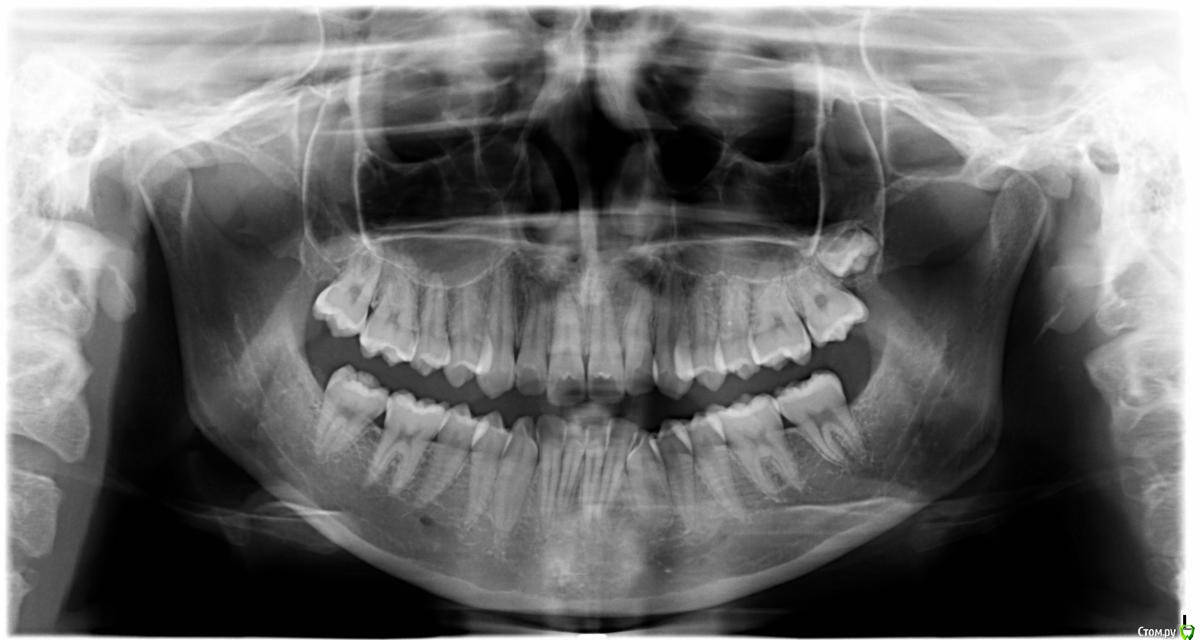

kamranchick Опубликовано 27 октября, 2015 Поделиться Опубликовано 27 октября, 2015 Попытался достать 2.8не получается, не видно зуба и все.Как вы думаете может стоит убрать 7ой зуб? так как он смотрит щечно? либо в стационар? либо руки-крюки?Разрез делал вертикальный от 6 зуба. Ссылка на комментарий

kamranchick Опубликовано 27 октября, 2015 Автор Поделиться Опубликовано 27 октября, 2015 Не щёчно располагается, убрал косточку оттуда, и пусто)7ку хотел убрать так как не в прикусе и наклонена щечно, ничего не видно за ней... Ссылка на комментарий

kamranchick Опубликовано 28 октября, 2015 Автор Поделиться Опубликовано 28 октября, 2015 Зачем к лору? Зачем наркоз?Убрать под инфильтацией и не паритсяЗуб в пазухе находится, попытался вытащить пылесосом не получилось, катается туда сюда, а обзора из-за 7 го зуба ничего не видно. из наклона, возможно просто опыта мало в таких ретенциях. Ссылка на комментарий